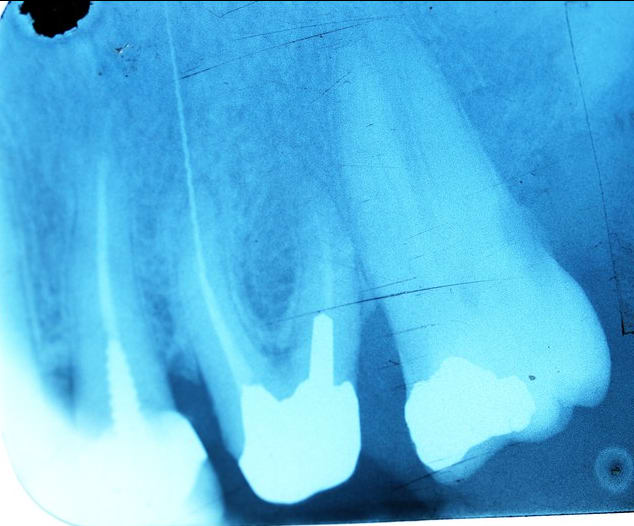

je me dévoue pour Souricette , j en ai une pour toi , et c est moi qui l ai fait :-)

c est cadeau , tu vas te régaler :-)

Je n’ai pas l’habitude de critiquer mais c’est vrai que c’est pas joli joli.

Maintenant, une fracture d’instrument c’est juste un alea thérapeutique.

caramba encore raté :-)

Y a pas un problème occlusal 🤔 ?

Il n'y a pas de radio pq je ne suis pas au cab mais elles montreraient sur deux piliers un manque d'obturation.

Manque d’obturation sur 2 piliers, j’avais la radio depuis le début !

" Manque d’obturation sur 2 piliers, j’avais la radio depuis le début ! "

Oui on l avait tous en tête , et alors ?

On a d ailleurs tous des radios de nos cas avec des manques , et alors ? et alors ce n est pas suffisant, il y a les symptômes associés, et 6 mois après pour prendre la décision de tout casser , le soit disant mal ne suffit pas .

Sauf a avoir des radios délirantes comme tu nous as montré .

Une radio seule n expliquant pas tout .